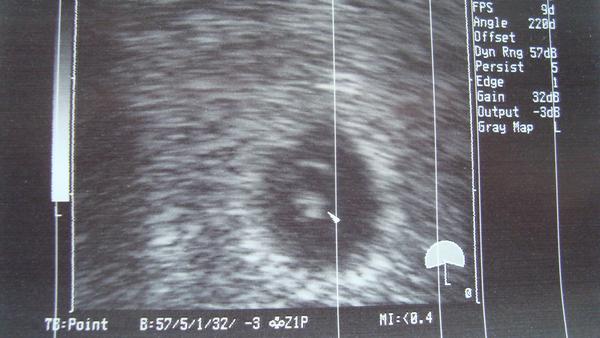

Ahoj holky!!! Tak mám za sebou první UZ 🙂 Byly to ráno hrozný nervy 😝 Takže... V děloze je jeden živý plod se srdeční akcí!!!!!!!!!!!!!!!!!!!!!!!!!!!!!!!!!! 😵 😵 😵 😵 jupí!!!! Mám hroznou radost 😵

@mariiianka Děkuju 🙂 😉 No končím 6tt, podle UZ 6+0, podle MS 5+6. To jo, pojede, ale zase se budu strachovat do další kontroly, aby srdíčko pořád tlouklo🙂

@barakara Děkuju 🙂 Úžasný pocit to je. Doktor je fakt hodně zkušenej a hned všechno našel. A srdíčko jsem hned viděla i já 🙂